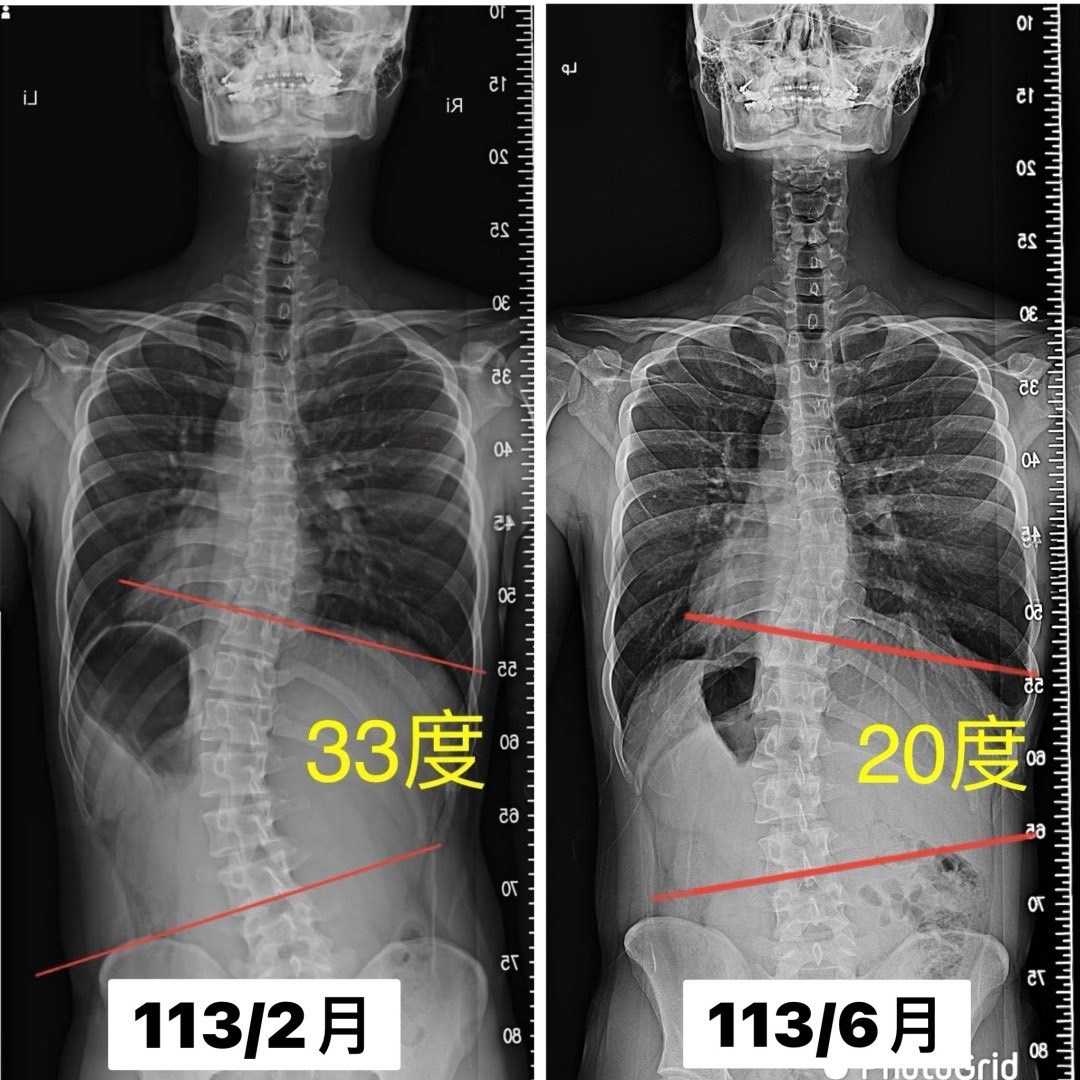

個案小諺(化名),就算生長板閉合,大學即將畢業的年紀,經過三個月的 #側彎矯正訓練,整整少了13度,創造驚豔的成果,從33度減少到20度

我常在課程的一開始就會建立雙方的默契,側彎矯正不是來找我就會進步,而是內化到日常生活,每天養成習慣,付諸實際行動做矯正訓練;小諺每天練習40分鐘,每天錄影交作業,3個月就有明顯的改變,相信每天努力不會白費

謝謝孩子跟爸媽的堅持,也期待下一位進步的你/妳~